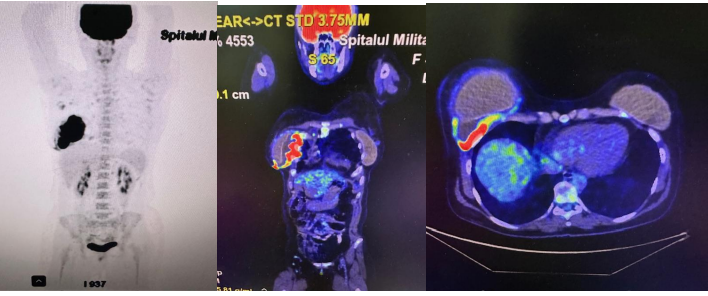

PET/CT revealsactive metabolic changes located around prosthetic implant in the right breast (Figure 4).

Figure 4: Active metabolic changes located around prosthetic implant in the right breast on PET/CT